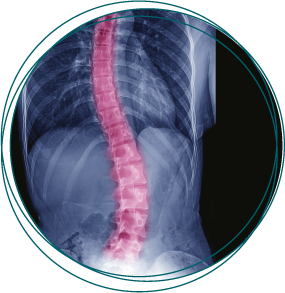

Dreidimensionale Skoliosetherapie

nach Katharina Schroth®

Die dreidimensionale Skoliosetherapie nach Katharina Schroth® mit Atmungsorthopädie ist ein seit vielen Jahren erprobter und weiterentwickelter Therapiestandard.